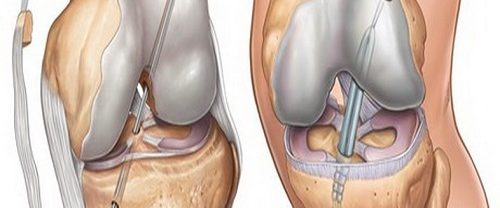

Transfix Tekniği ile Ön Çapraz Bağ Yırtılması ve Tedavi Yöntemleri Transfix Tekniği | Ön çapraz bağ yırtılması, genellikle spor yaralanmaları veya ani dönme hareketleri sonucu ortaya çıkan bir durumdur. Bu yırtık, dizin stabilitesini etkileyebilir ve günlük aktivitelerde ve spor yaparken ağrı ve kısıtlılığa neden olabilir. Ön çapraz bağ yırtılması olan birçok kişi için cerrahi müdahale gerekebilir.…

Diz Artroskopisi Nedir? Diz artroskopisi, diz bölümlerinin iç bölümünün küçük bir kamera (artroskop) ile girilerek yapılan cerrahi bir işlemdir. Bu işlem, iç dizinin daha ayrıntılı ve tedavisi için kullanılır. Artroskop, cerrahın dizinin içindeki yapıların net bir şekilde görülmemesini sağlar. Amacı ve Hedefleri Tanısal Amaç : Dizdeki kesin teşhisini koymak için kullanılır. Bu, menisküs yırtıkları, bağ…